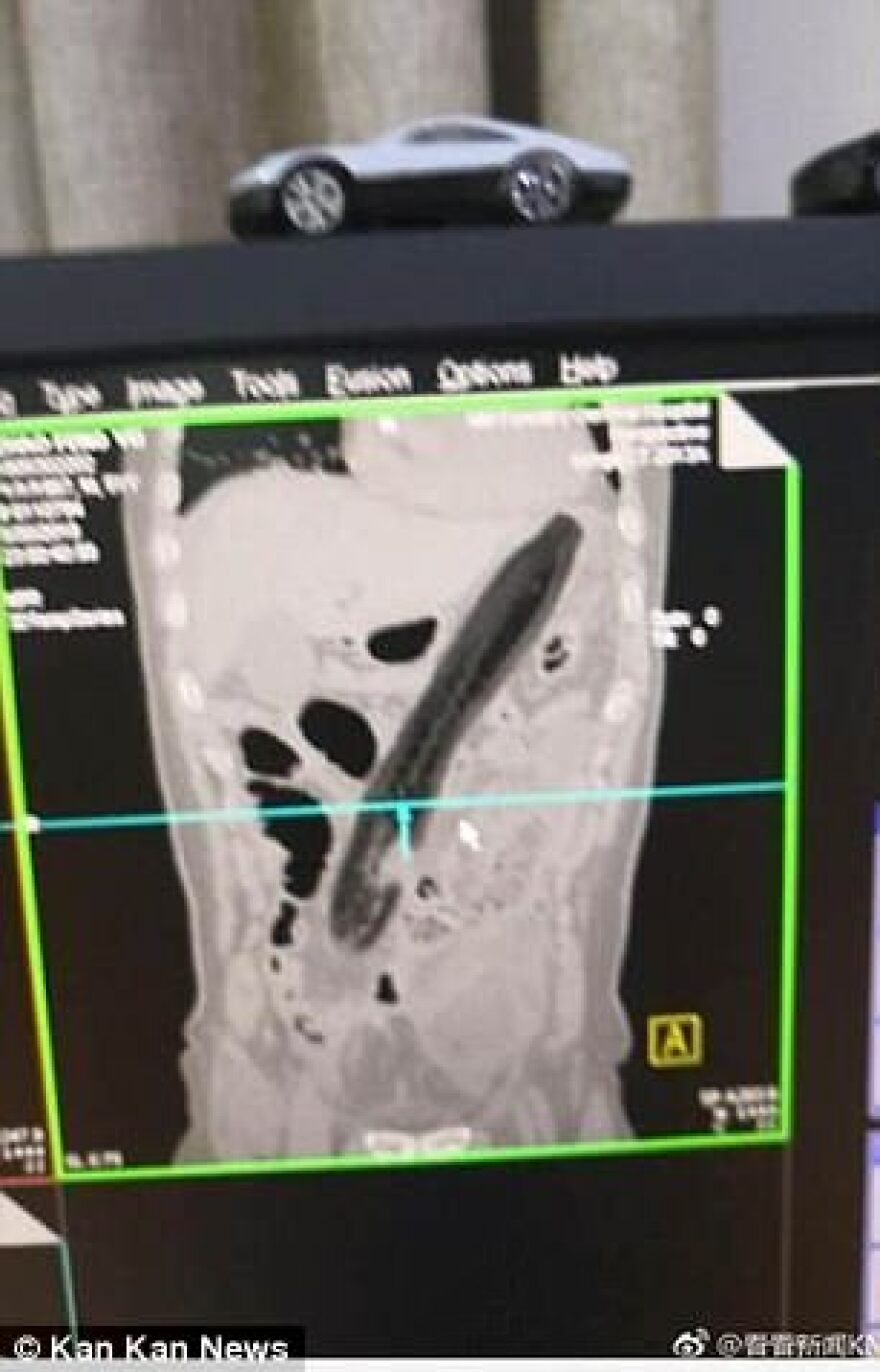

Όταν ο 50χρονος υποβλήθηκε σε ακτίνες για να διαπιστωθεί από τι πάσχει, οι γιατροί διέκριναν με μεγάλη έκπληξη ένα τεράστιο αντικείμενο να έχει κολλήσει στο έντερο το ασθενούς.

Όταν τον ρώτησαν τι μπορεί να είναι αυτό, εκείνος «εξομολογήθηκε» ότι ήταν μία... τεράστια μελιτζάνα!

Η αποκάλυψη ωστόσο, δεν ήταν το... αποκορύφωμα της ιστορίας, καθώς 50χρονος Κινέζος είχε να πει πολλά ακόμα. Όπως είπε στους γιατρούς, έπασχε για τέσσερις ολόκληρες ημέρες από δυσκοιλιότητα, γεγονός που τον είχε ταλαιπωρήσει σε πολύ μεγάλο βαθμό. Μετά από τέσσερις ημέρες έντονων πόνων, ο Κινέζος βρήκε μία τεράστια μελιτζάνα και την... έβαλε στον πρωκτό του σαν... κλύσμα, προκειμένου να αντιμετωπίσει το πρόβλημά του!

Τα παραπάνω υποστήριξε ο 50χρονος άνδρας, προκειμένου να δικαιολογήσει την... παρουσία του αντικειμένου στο παχύ του έντερο. Όποιος και αν ήταν, τέλος πάντων, ο λόγος που έβαλε τη μελιτζάνα στον πρωκτό του, το πρόβλημα δημιουργήθηκε όταν... έχασε τον έλεγχο στο... χειρισμό! Η μελιτζάνα εισχώρησε πιο βαθιά και... τα υπόλοιπα φάνηκαν στην ακτινογραφία!

Τα πειστήρια των εξετάσεων...